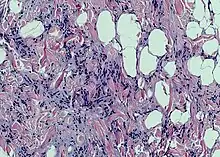

| Spindle cell lipoma | |

Spindle cell lipoma is an asymptomatic, slow-growing subcutaneous tumor that has a predilection for the posterior back, neck, and shoulders of older men.[1]: 625 [2]